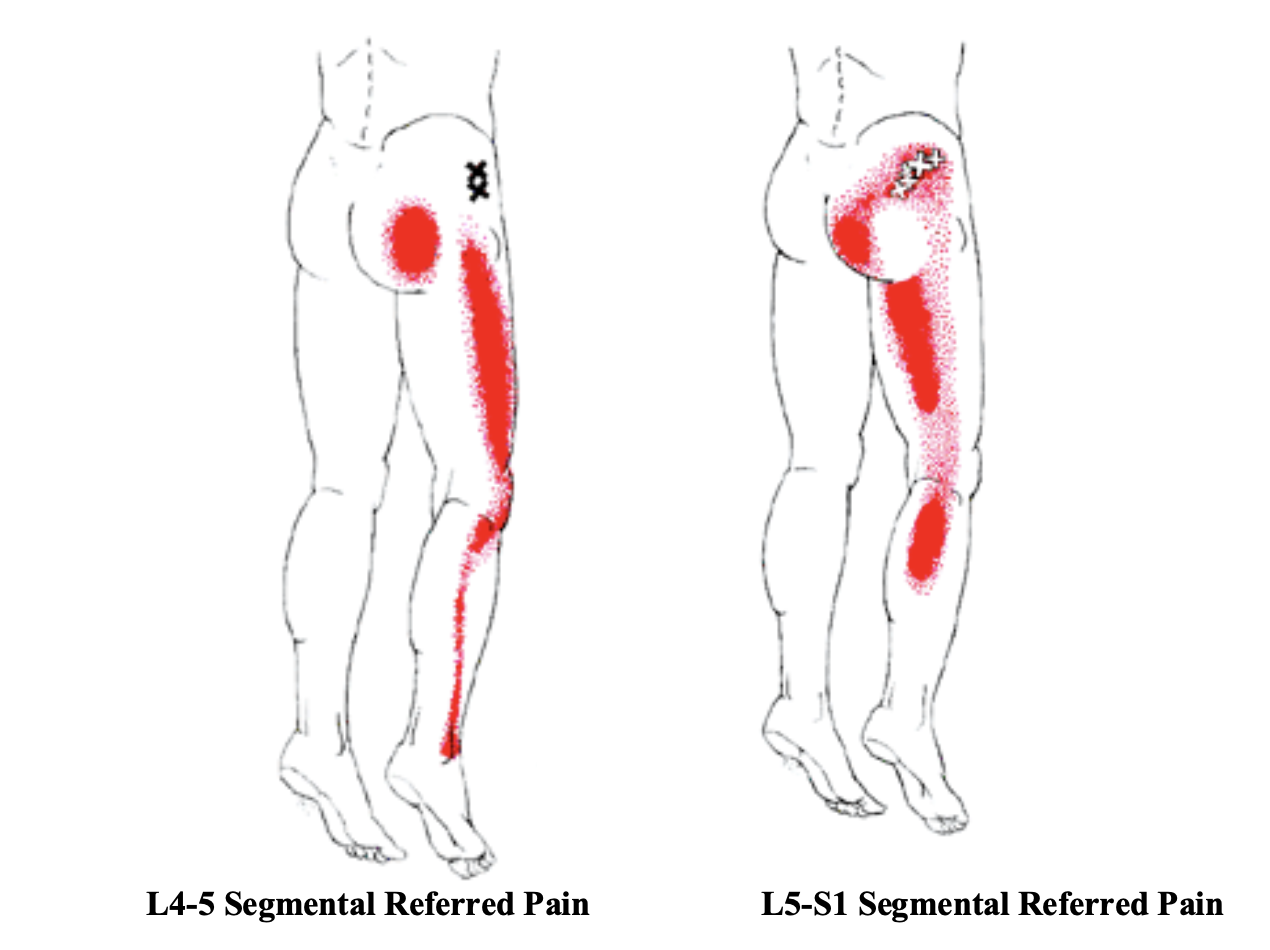

Diagnosing Lateral Thigh Pain IT band syndrome Hip Bursitis and

Product Name: Muscle on outside of clearance thighMuscle Strains in the Thigh Florida Orthopaedic Institute clearance, Lateral leg pain more than just the IT Band Revo Physiotherapy clearance, 6 Power Packed Outer Thigh Exercises For Lower Body Strength DMoose clearance, 10 Best Thigh Exercises For Leg Day Workouts Steel Supplements clearance, Diagnosing Lateral Thigh Pain IT band syndrome Hip Bursitis and clearance, Can Rolling Your IT Band Make It Worse Functional Performance clearance, Thigh muscles side view Human anatomy Leg anatomy Human muscle clearance, Quad Muscles Function and Anatomy clearance, Rolling of the IT band anatomy of outer thigh muscles blog post clearance, Vivian Grisogono ABOUT THE FRONT THIGH MUSCLES clearance, Iliotibial band syndrome ITBS clearance, Adductor muscles of the hip Wikipedia clearance, The Secret to Resolving IT Band Syndrome using Thai Massage Thai clearance, Professor Ernest Schilders The London Hip Arthroscopy Centre clearance, Muscles of the Posterior Thigh Hamstrings Damage TeachMeAnatomy clearance, Runners Knee also known as ITB Syndrome Do You Have It and How clearance, The Physio Detective The ITB 5 things you probably haven t clearance, Diagnosing Lateral Thigh Pain IT band syndrome Hip Bursitis and clearance, Vivian Grisogono ABOUT THE FRONT THIGH MUSCLES clearance, Anatomy Of Human Thigh Muscles Greeting Card clearance, Muscles of the Human Body clearance, Understanding Iliotibial Band Syndrome Saint Luke s Health System clearance, Diagnosing Lateral Thigh Pain IT band syndrome Hip Bursitis and clearance, Meralgia paresthetica Symptoms and causes Mayo Clinic clearance, Foam rolling IT band Dos and don ts clearance, What is the Vastus Lateralis Muscle Orchard Health Clinic clearance, What is the muscle on the back of your thigh Quora clearance, IT band Friction Syndrome Ortho Rhode Island clearance, Why does the top of my left thigh ache when raising it up Quora clearance, Anatomy of Leg Muscles Plus How to Make the Most of Leg Exercises clearance, Meralgia Paresthetica Neuromuscular and Electrodiagnostic Clinic clearance, Soft Tissue Reconstruction of the Lateral Thigh and Hip SpringerLink clearance, Why Is Your Thigh In Pain 6 Common Causes Carex clearance, Anatomy of the Hamstring Upper Leg clearance, Muscle Knots in Side of Leg IT Band Tiger Tail USA clearance, Front Thigh Pain Anterior Thigh Pain Symptoms Causes Treatment clearance, Pelvic hip and thigh muscles of the right side of the body Part clearance, Outer Quad Exercises 7 Must Do Exercises Fitbod clearance, The Hip Abductor Muscles Trochanteric Bursa and Lateral Outside clearance, Muscles of the hips and thighs Human Anatomy and Physiology Lab clearance, Anatomy of the Piriformis Muscle Spine health clearance, Why Does The Outside Of My Hip Hurt What to Do About It clearance, Vastus lateralis muscle Wikipedia clearance, What is IT Band Syndrome and How Can I Fix It clearance, IONA Physiotherapy WHAT AND WHERE IS THE ILIOTIBIAL BAND ITB clearance, Groin Strain Symptoms Causes Treatment Rehabilitation Exercises clearance, Simple Ways to Stretch Your Outer Thighs 9 Steps with Pictures clearance, Meralgia Paresthetica Causes Symptoms Treatment clearance, Knee Muscles Anatomy Function Injuries Knee Pain Explained clearance, How to Cure Thigh Muscle Pain clearance.